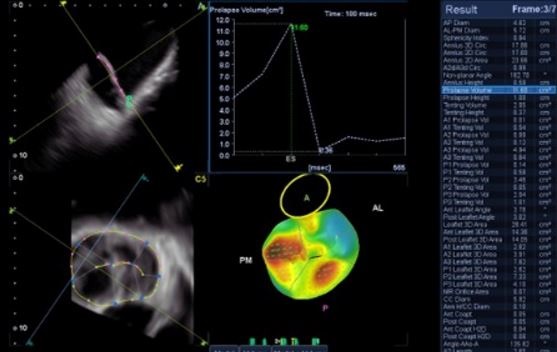

Аналіз мітрального клапана в 4D (4D MVA)

Цей унікальний інструмент забезпечує анатомічну та функціональну оцінку мітрального клапана, проводячи близько 40 вимірювань за 30 секунд, та допомогає лікарю при плануванні інтервенційного втручання, наприклад для операції транскатетерної імплантації мітрального клапана.

- Функціональна оцінка мітрального клапана

- Автоматизовані вимірювання мітрального клапана з виведенням в реальному часі більш ніж 40 показників

- Реконструкція мітрального клапана візуалізує форму стулок клапана, що допомагає оцінити пролапс або деформацію.